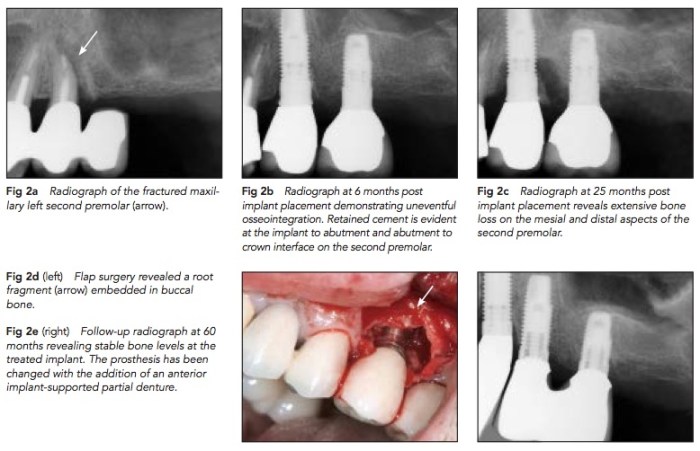

在之前的文章中有提到故意留下buccal的root fragment來保留buccal的骨頭. 這篇文章就是相反的, 他是case report, 主要是植牙時候沒有注意到有牙根碎片就種下去. 結果是一半成功一半失敗, 這樣看起來是不是不要冒險比較好呢?